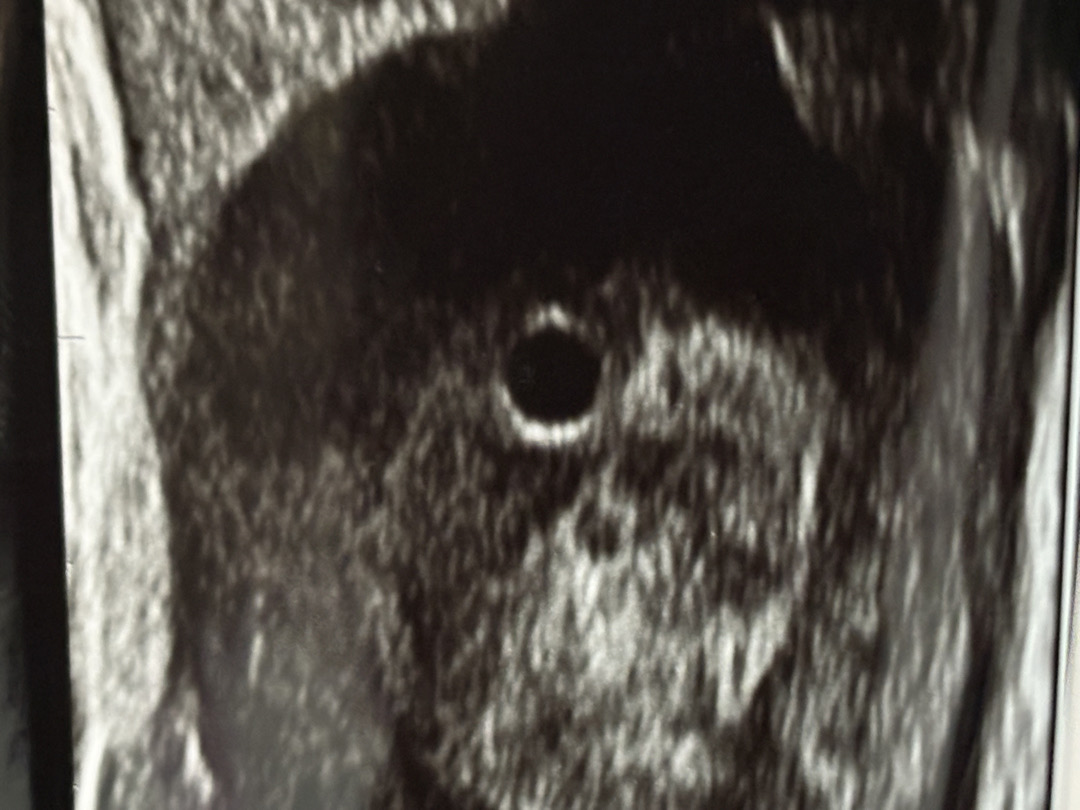

딱 5주차 어제 아기집 보고 왔어요

난황은 못보고 아기집만 확인했어요 근데 4주차부터 계속 무기력하고 텐션떨어지고 우울하고 피곤하고 저만 그런가요 ㅠㅠ?